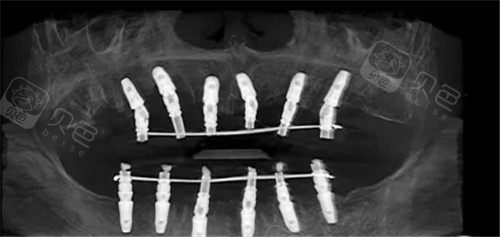

种植牙过程图示